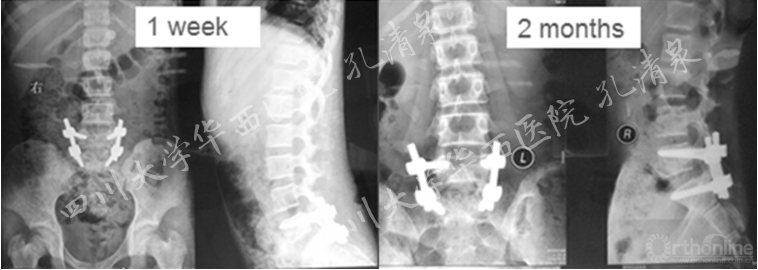

治疗:经后路腰5-骶1固定、腰5滑脱、骶1骨骺复位、椎管减压、后外侧植骨融合术,术后患者双下肢麻木消失,肌力恢复正常,术后2月复查发现轻度的腰椎侧凸,术后三年复查存在27°的腰椎侧凸,取出内固定,术后六年半时CT复查示腰5和骶1高度增加2mm,残留27°的腰椎侧凸。

图9 术后一周复查见滑脱复位良好,无侧凸;术后两月复查,复位情况良好,可见轻微腰椎侧凸

图10 术后两年半复查提示腰段侧凸加重,整个冠状面平衡尚可